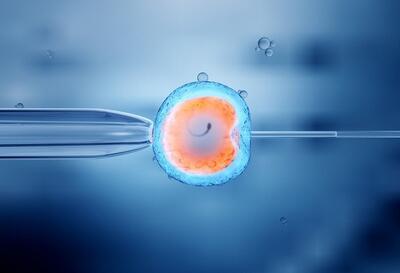

رئیس مرکز ناباروری مولود بیمارستان علی بن ابیطالب زاهدان گفت: این مرکز با هدف ارائه خدمات پیشرفته درمان ناباروری و با بهرهمندی از سه پزشک مجرب فلوشیپ ناباروری و سه دکتر بیولوژی تولیدمثل که بهعنوان جنینشناس فعالیت میکنند، خدمات تخصصی ارائه میدهد.